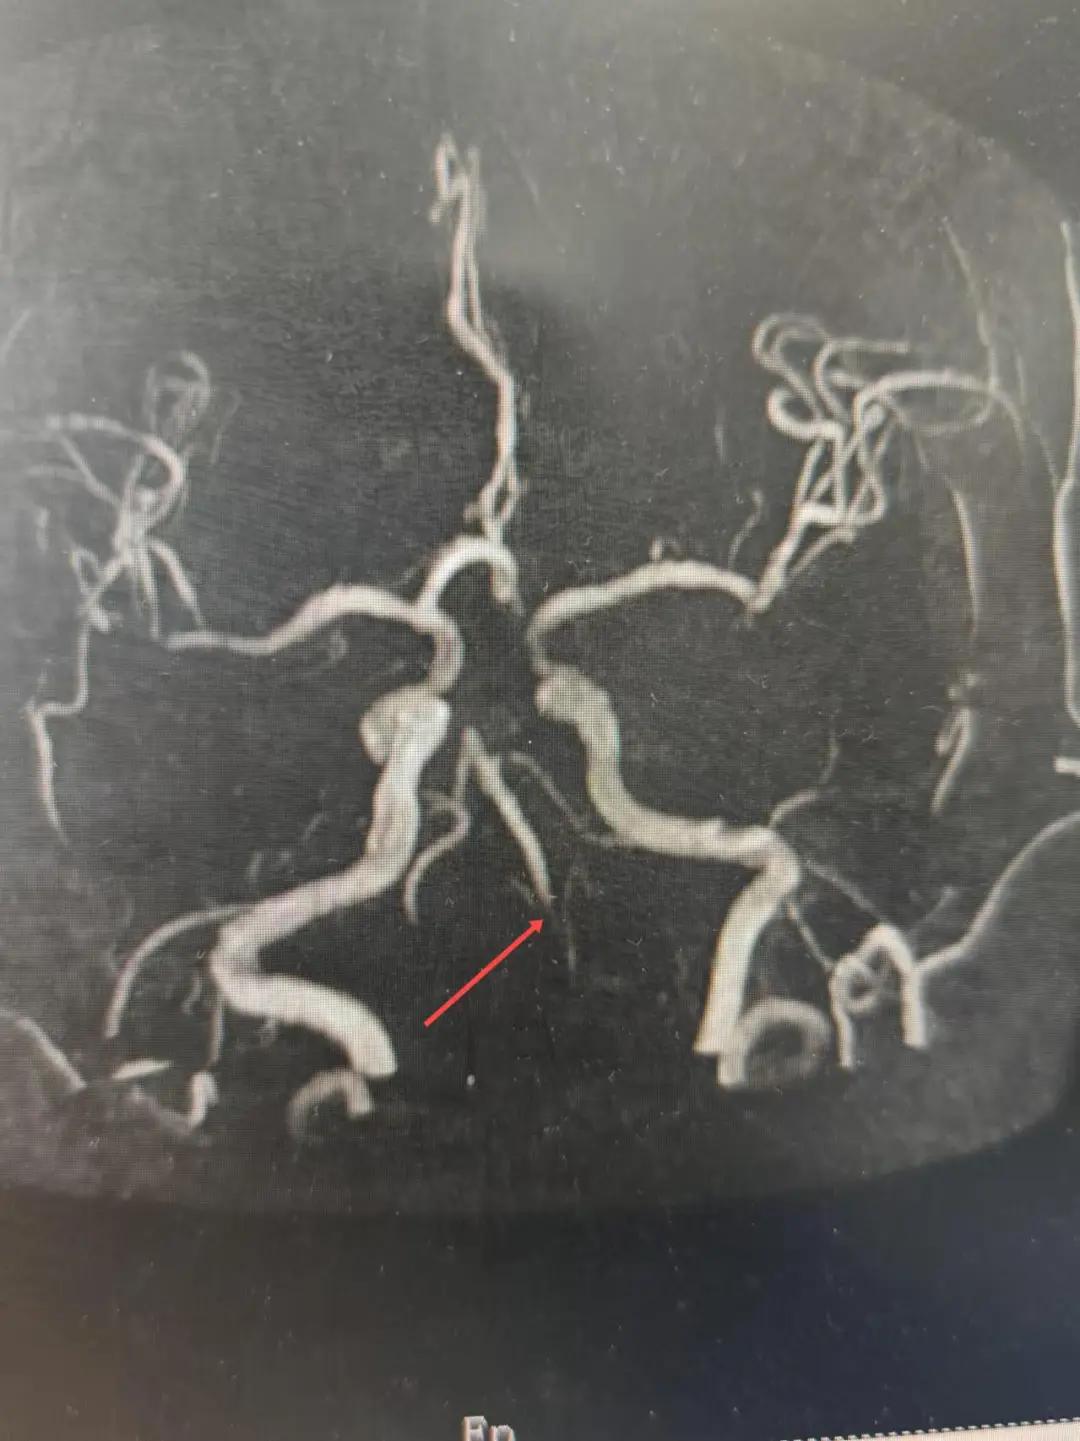

磁共振MRA提示基底動(dòng)脈閉塞

在經(jīng)造影后,主刀醫(yī)生腦一科副主任楊慶堂發(fā)現(xiàn)患者基底動(dòng)脈下段重度狹窄且狹窄段以遠(yuǎn)有大負(fù)荷血栓,其狹窄處考慮為動(dòng)脈夾層,手術(shù)難度及風(fēng)險(xiǎn)較大。楊慶堂副主任在彭壯副主任醫(yī)師的協(xié)助下運(yùn)用spaceman(太空人)技術(shù),中間導(dǎo)管抵近血栓抽吸配合支架拉栓,成功開通血管。再次造影可見基底動(dòng)脈管腔明顯增寬,遠(yuǎn)端血管顯影良好,且等待20分鐘后造影仍顯示血流通暢。楊慶堂副主任考慮到本次手術(shù)時(shí)間不宜過長,現(xiàn)患者基底動(dòng)脈及分支前向血流維持良好,給予其抗栓藥物應(yīng)用后結(jié)束手術(shù),并建議患者3個(gè)月后復(fù)查造影,明確其基底動(dòng)脈夾層情況。

取栓后血管管腔增寬,前向血流良好